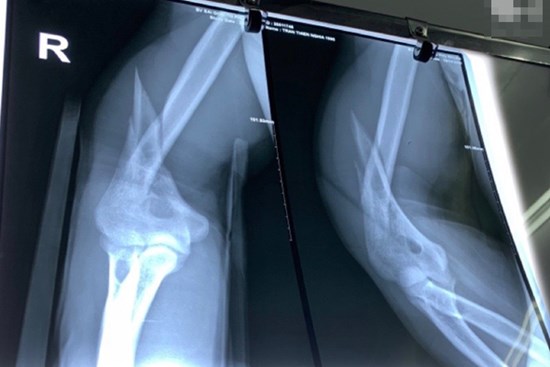

Bị gãy đôi cánh tay khi vật tay với bạn xem ai khỏe hơn

Một nam thanh niên ở Brazil đã bị gãy cánh tay trong khi vật tay với bạn.